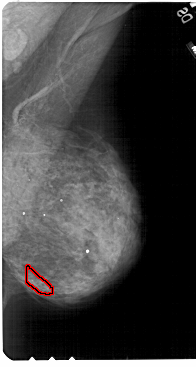

A_1810_1.RIGHT_CC

RIGHT_CC LINES 4996 PIXELS_PER_LINE 2626 BITS_PER_PIXEL 12 RESOLUTION 43.5 OVERLAY

FILE: A_1810_1.RIGHT_MLO.OVERLAY

TOTAL_ABNORMALITIES 1

ABNORMALITY 1

LESION_TYPE CALCIFICATION TYPE PLEOMORPHIC DISTRIBUTION CLUSTERED

ASSESSMENT 4

SUBTLETY 2

PATHOLOGY BENIGN

TOTAL_OUTLINES 1

BOUNDARY